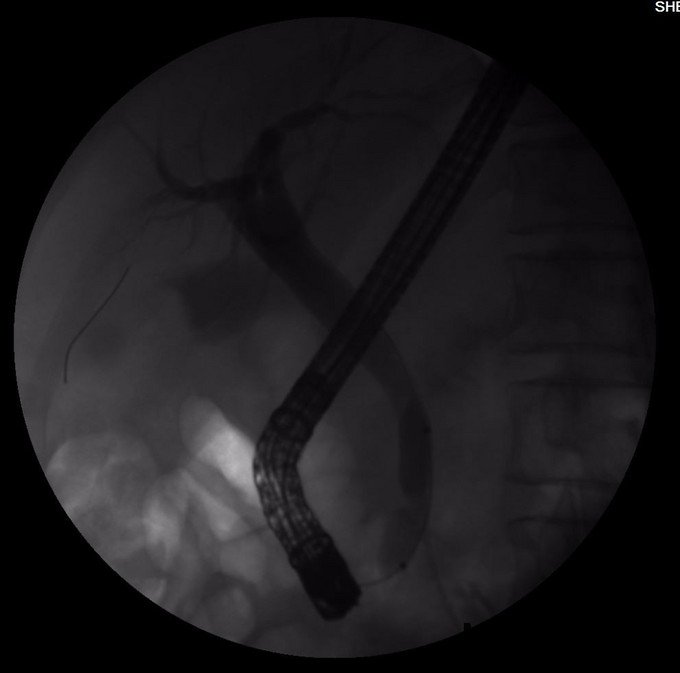

诊断: 胆囊结石 胆总管结石 胆源性胰腺炎 治疗:胃肠减压,抗炎,补液,抑酶,抑酸治疗,急诊内镜至十二指肠,见十二指肠乳头肿胀,选择性胆管插管顺利,造影见胆总管直径12mm,末段可见数处充盈缺损,最大大小约6mm,行乳头肌切开(EPT),以12mm球囊扩张乳头(1ATM,40s)后,取石球囊取出黄色结石1枚及少许泥沙样结石,球囊及盐水清理胆道,再次造影见胆总管内无充盈缺损,留置鼻胆引流管,选择性胰管插管顺利,留置5Fr5cm胰管塑料支架一枚。次日,患者血淀粉酶恢复正常,血脂肪酶降至156U/L,腹痛明显缓解。EPT第二日,全麻下腹腔镜胆囊切除术(LC),手术顺利,术中发现胰腺无坏死,未处理胰腺,LC术后2天再次经EPT留置的ENBD管造影,未发现胆总管结石,复查血淀粉酶及脂肪酶,均恢复正常,拔管出院。